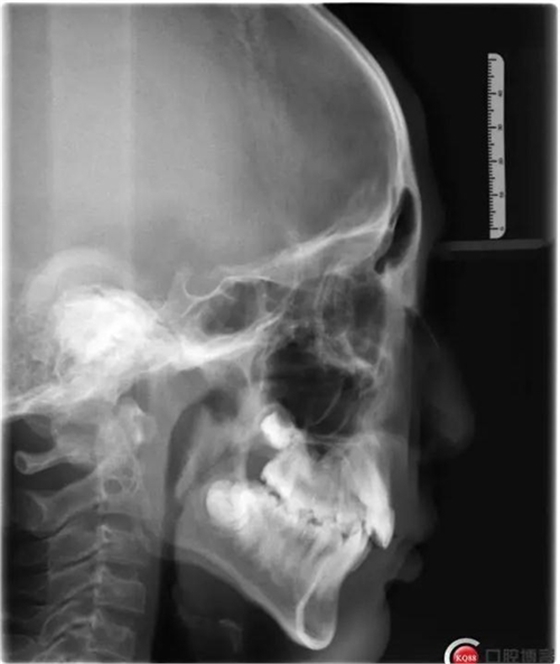

1500866161_694151.jpg1500866311_947305.jpg

此病例主要考慮的是垂直骨面型,矢狀骨面型,前牙覆合覆蓋及尖牙關(guān)系,側(cè)貌